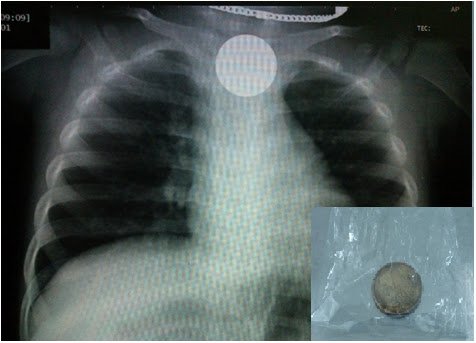

- Nguyên nhân từ đường dẫn khí: Dị vật, hen phế quản, phù hoặc co thắt thanh môn do phản vệ, đợt cấp bệnh phổi tắc nghẽn mạn tính (COPD)